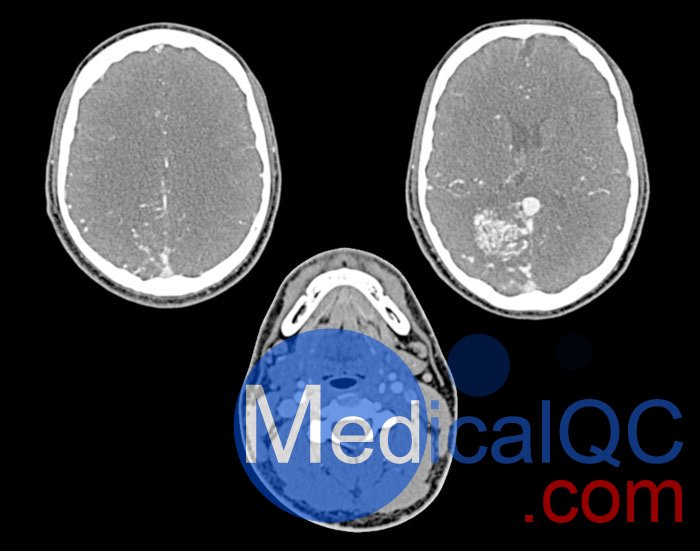

WEK51-04 CTA AVM頭部模體,WEK51-04 CT血管造影頭模模擬動(dòng)脈期造影劑增強(qiáng)頭部(CT 血管造影)。它覆蓋了第五頸椎的頂點(diǎn)。右半球有動(dòng)靜脈畸形。

該模型可用于 CT(包括 CBCT)以評(píng)估和優(yōu)化成像性能以及支持 AI 的診斷。它也適用于培訓(xùn)目的。

該模型提供了對(duì)血管結(jié)構(gòu)、軟組織和骨組織的詳細(xì)和逼真的模擬,包括淋巴結(jié)等小細(xì)節(jié)。空隙中填充著約-160HU的纖維素-聚合物復(fù)合材料。

對(duì)頭頸部血管進(jìn)行逼真的模擬,直至主動(dòng)脈弓、骨骼和軟組織。兩側(cè)頸動(dòng)脈分叉處頸內(nèi)動(dòng)脈鈣化,右側(cè)輕度狹窄。

WEK51-04 CTA AVM頭部模體,WEK51-04 CT血管造影頭模成像效果圖: